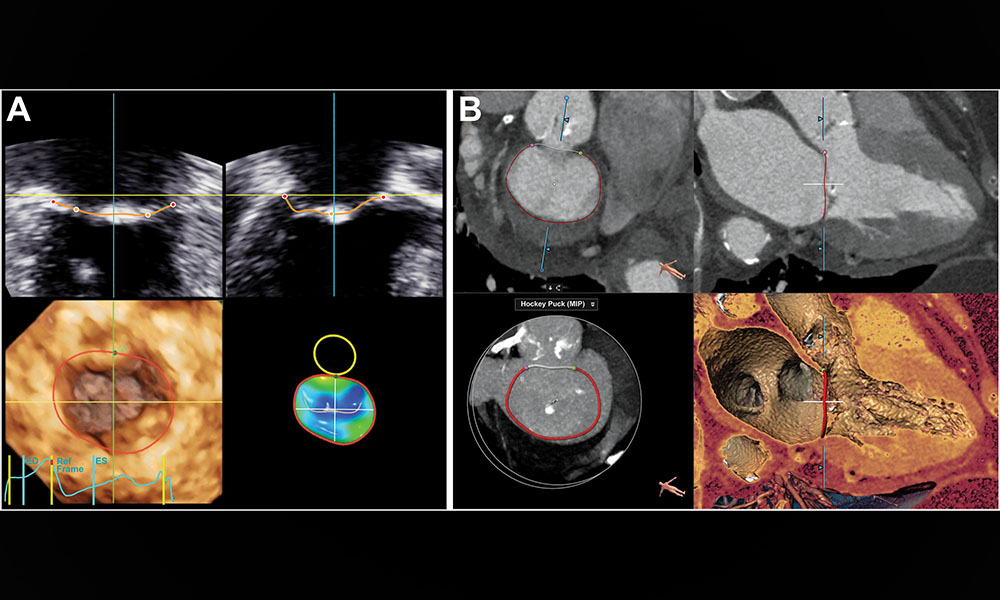

Mitral annulus measurements are critical for effective transcatheter mitral valve implantation preprocedural planning. This pilot study aimed to evaluate the potential of 3D TTE, in comparison to CT, as a method to screen patients for excessive MA size. bit.ly/3zMuFLJ

Mitral annulus measurements are critical for effective transcatheter mitral valve implantation preprocedural planning.

This pilot study aimed to evaluate the potential of 3D TTE, in comparison to CT, as a method to screen patients for excessive MA size. bit.ly/3zMuFLJ